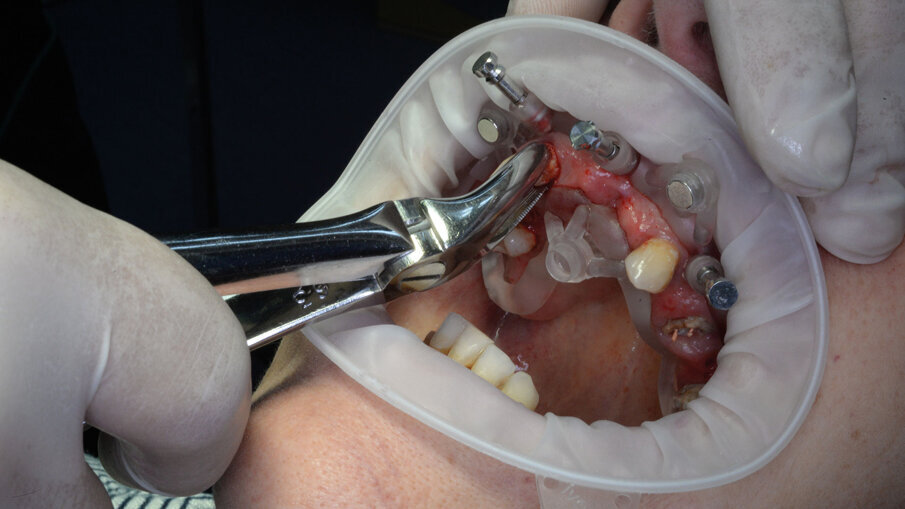

Per la realizzazione delle dime chirurgiche abbiamo utilizzato il nuovo modulo Sculpt rilasciato per lo stesso software di chirurgia guidata BNX 3D GUIDE. Questo nuovo modulo permette di creare una serie di dime scomposte da utilizzare in sequenza per eseguire le estrazioni e l’osteoplastica necessaria, rimanendo sempre all’interno di un flusso di lavoro guidato. Le dime si adattano l’una all’altra grazie a supporti di accoppiamento che contengono piccoli magneti con polarità opposta. L’azione di questi magneti permette di ritrovare velocemente e fedelmente sempre la stessa posizione delle dime anche se dovessimo rimuoverle per poi reinserirle. Affidandoci alla stabilità ancora presente su alcuni denti abbiamo progettato una prima dima ad appoggio dentale che permettesse il corretto posizionamento della dima esterna che sarà l’unica a rimanere sempre in posizione fino alla fine dell’intervento (Fig. 9). Una volta stabilizzata con i pin di stabilizzazione e rimosso il posizionatore, si è potuto apprezzare la bellezza della metodica che permette un’ampia visione e molto spazio a disposizione per poter eseguire le fasi chirurgiche preliminari di preparazione (estrazioni e sollevamento di piccoli lembi). Liberata l’arcata dall’ingombro dei denti e di tessuti in eccesso si è potuto posizionare la dima di perforazione nella corretta posizione grazie alla presenza della dima esterna rimasta in posizione (Figg. 10-13).

Alla preparazione dei tunnel implantari è seguito il loro inserimento sempre con tecnica guidata utilizzando gli appositi montatori forniti nel kit, avendo cura di far combaciare le tacche di riferimento dei montatori con le linee di repere preventivamente disegnate sulla dima così da ottenere il corretto posizionamento dei 2 mua angolati previsti nel settore anteriore (Fig. 14). In fase chirurgica il posizionamento dei mua è stato ulteriormente facilitato dalla presenza di un doppio esagono presente all’interno dell’impianto che rende possibili ulteriori aggiustamenti “di fino” del componente protesico. Avvitate tutte le torrette il provvisorio è stato poi cementato con cemento duale dedicato utilizzando un foglietto di diga preforato per facilitarne la cementazione (Figg. 15, 16).